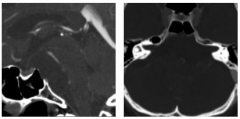

脊索瘤和软骨肉瘤不能仅仅根据影像学特征来区分,无论是在CT还是MRI中。较近,Yeom等人回顾性分析了19例经组织学证实的脊索瘤和软骨肉瘤患者的常规和...